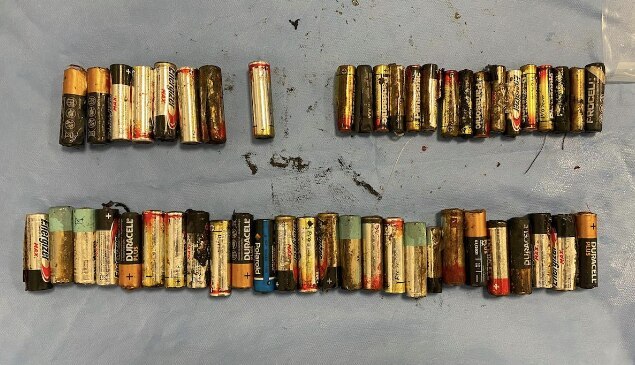

개복수술을 통해 A씨의 몸에서 제거된 건전지들./아일랜드 의학 저널

A씨의 몸에서 발견된 건전지들./아일랜드 의학 저널

결국 A씨가 복통과 식욕부진 등을 호소하기 시작하자 의료진은 개복수술을 통해 남은 건전지 46개를 꺼냈다. 결장에 있던 4개의 건전지는 직장을 통해 항문으로 제거했다. 당시 A씨의 위는 건전지 무게 때문에 치골까지 늘어난 것으로 전해졌다. 건전지 제거 이후 A씨의 상태는 빠르게 회복됐다고 한다.